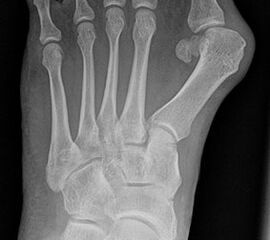

Bei einem juvenilen Hallux valgus handelt es sich um eine schon im Kindes – oder Adoleszentenalter 1 bestehende Valgusdeviation der großen Zehe bei Spreizfuß mit vergrößertem Intermetatarsalwinkel I / II aufgrund einer Adductionsstelllung des Metatarsale I – Metatarsaus primus varus.

Im Gegensatz zum Hallux valgus des Erwachsenen ist die Valgusabweichung der großen Zehe meist geringer ausgeprägt als bei Erwachsenen, der Intermetatarsalwinkel oft stark vergrößert. Die Angaben ab wann der Intermetatarsalwinkel als vergrößert gilt schwanken zwischen > 9° 2 und >14°3. Das Ausmaß der Beschwerden korrelieren nicht mit dem Auftreten und dem Schweregrad der Deformität (Zollinger 1990, Zollinger 1993). Begünstigend wirkt eine Schrägstellung des ersten Tarsometatasalgelenkes (Hefti 1998) und eine Hypermobilität dieses Gelenkes 2 in Kombination mit einer Bindegewebsschwäche. Häufig liegt eine positive Familienanamnese vor. In einer Untersuchung von Coughlin fand sich eine Vererbung über die mütterliche Linie in 72%, ein milder bis stark ausgeprägter Knick-Senkfuß in 17% (das entspricht der Quote von Knick-Senkfüßen in der Normalbevöl­kerung) aber in 22% ein Pes adductus, das ist wesentlich mehr als in der Normalbevölkerung zu erwarten wäre 4. Auch für Hefti (1998) gilt der Pes adductus als Komponente des Sichelfußes als begünstigend. Zur Inzidenz des Hallux valgus juvenilis finden sich je nach Autor verschiedene Angaben. Nach Auswertung von Schuluntersuchungen liegt die Häufigkeit zwischen 1,6 % bis 17% 56. Häufig tritt die Fehlstellung doppelseitig auf. Der Anteil der betroffenen Mädchen liegt 4-5x höher als bei Jungen (Lamprecht 2015).

Röntgen

Standard ist die belastete Röntgenaufnahme des Fußes dorso-plantar und seitlich. Günstig ist eine Röhrenkippung von 10°-20°, um die Gelenke der Lisfranc-Linie einsehen zu können.

• Hallux valgus Winkel

• Hallux valgus interphalangeus Winkel

• Intermetatarsalwinkel I zu II

• Distaler Metatarsale Gelenkwinkel (PASA)

Tabelle 1: Normwerte der Winkelmaße

Intermetatarsalwinkel Hallux valgus Winkel

Normalwerte < 10° < 20°

Leichte –mittelgradige Fehlstellung 10°- 16° 20°- 40°

Schwere Fehlstellung > 16° > 40°